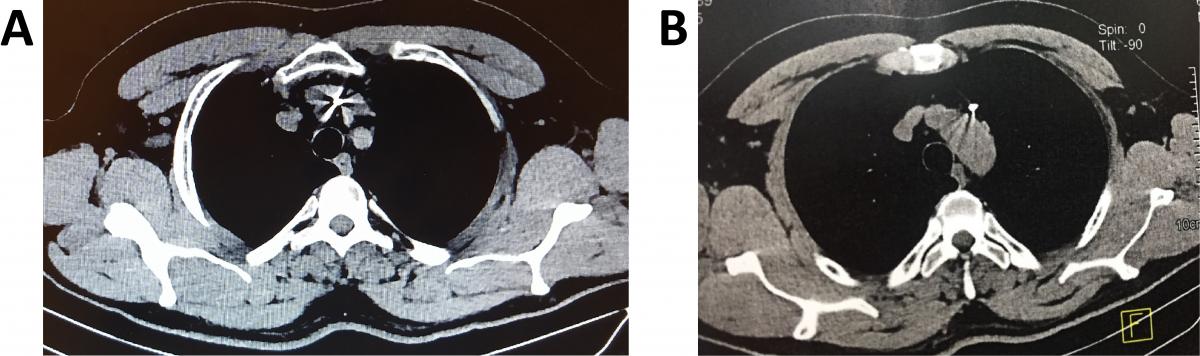

A chest computed tomography (CT) showed that the K-wire migrated through the anterior mediastinum into the left upper lobe (Figures 2A and 2B). In addition, a chest CT showed that the K-wire was encroaching on the left brachiocephalic vein, posing a risk to extraction of the foreign body (Figure 3A), and that it was anterior to the aortic arch (Figure 3B).

Figure 3. A) Chest CT (axial plane) showing the K-wire encroaching on the left brachiocephalic vein, posing a risk for extraction. B) Chest CT (axial plane) showing the K-wire in the anterior mediastinum in relation to the aortic arch.